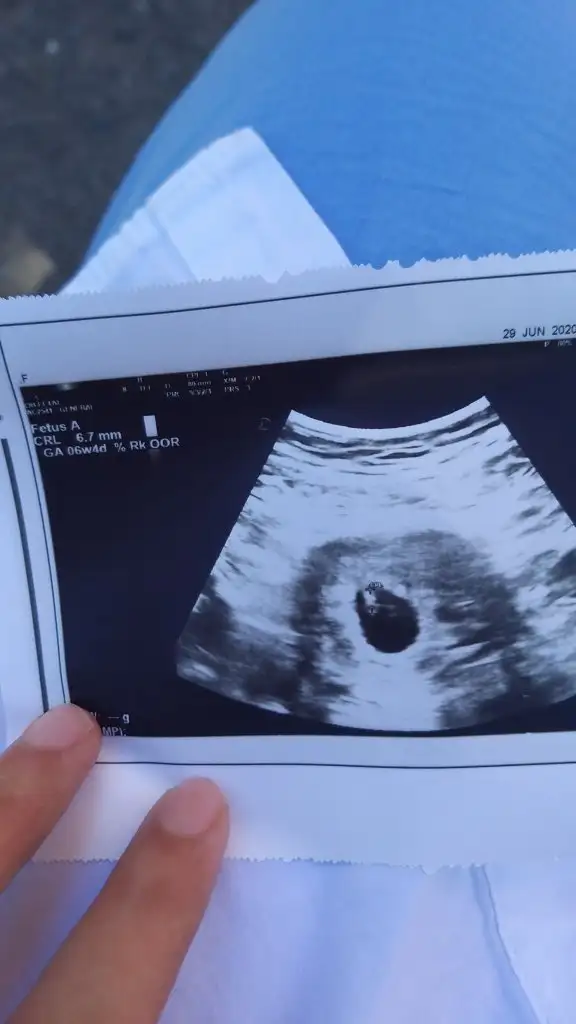

Kızlar doktordan geliyorum bebeğimin kalp atışlarını duyduk şükür biraz cılızdı çünkü 7 haftalık değil de 6+1 miş geç döllenme dedi doktor sat 17 mayıs olarak güncelledi. Herkesten güzel haberler bekliyorum

Bebeği gördük kalp atışını doktor gördü. Normalde 8+2'yim ultrasona göre 6+4 dedi. Kalp atışını duymak için haftaya gel dedi. Kan ve idrar verdim. Onlara da bakacak. Güzel gidiyor maşallahgorursnuz inşallah